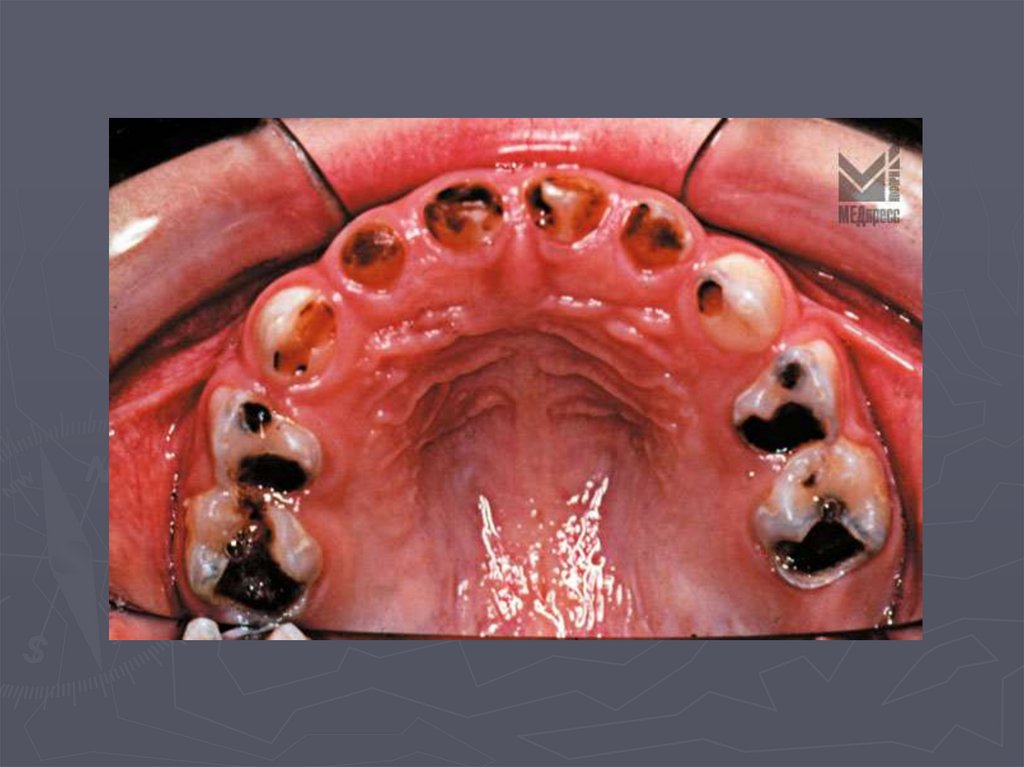

При декомпенсированной форме кариеса:

► индекс кп, КПУ, кп+КПУ до 7 и более;

► отмечается высокий процент осложненного

кариеса;

► развиваются частые обострения в ранее

депульпированных зубах;

► осложнения в зубах, ранее леченных по поводу

среднего и глубокого кариеса;

► у этой категории детей больше показаний к

удалению зубов;

► в одном зубе может быть несколько кариозных

полостей;

При декомпенсированной форме кариеса

(продолжение):

► кариозные полости преимущественно

локализуются на апроксимальных поверхностях;

► наблюдается частое выпадение пломб;

► часто развивается вторичный кариес;

► определяется высокий прирост кариеса .

Декомпенсированная форма кариеса

развивается у детей ослабленных, часто

болеющих, имеющих хронические соматические

заболевания.